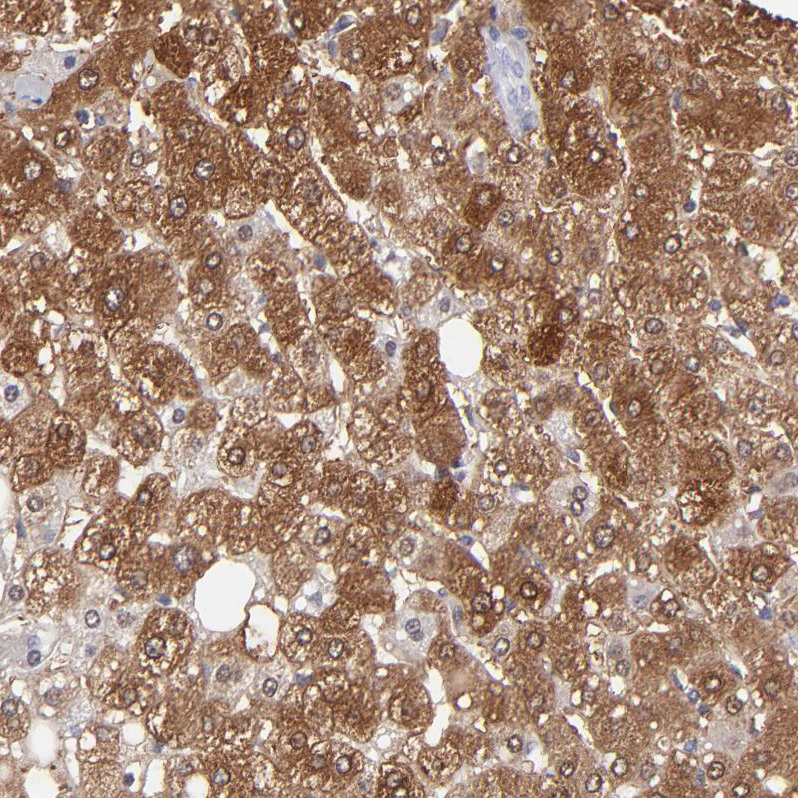

Immunohistochemistry analysis in human kidney and tonsil tissues using HPA002198 antibody. Corresponding ALDOB RNA-seq data are presented for the same tissues.